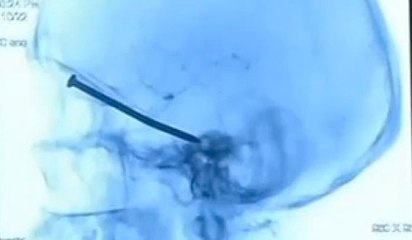

Un homme se fait retirer un criquet vivant de l’oreille